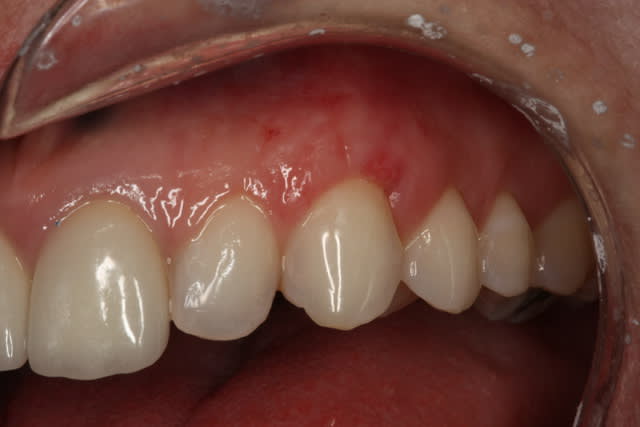

Comme on voit pas bcp de muco sur eugenol

P'tite 23 qui montrait trop de racine

Les 2 dernières photos sont à la dépose des fils (14 jours)